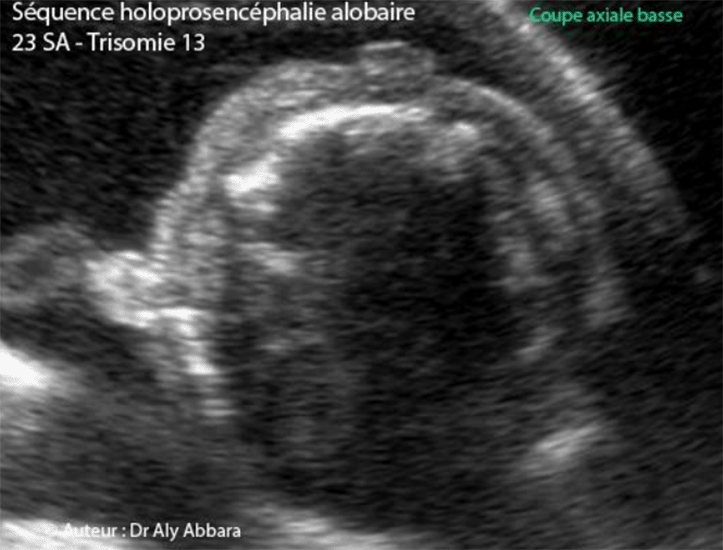

Images échographiques montrant, dans le cadre d'une holoprosencéphalie alobaire et trisomie 13, sur des coupes axiales du pôle céphalique fœtal, la présence d'une hypoplasie du pavillon de l'oreille externe et d'un proboscis. Le profil fœtal met bien en évidence la présence du proboscis frontal (au dessus du globe oculaire médiane unique), puis l'arhinie. Dans le cas présenté dans cet article, le fœtus est trisomique 13 âgé de 23 SA. L'étude de la morphologie révèle la présence d'autres anomalies en dehors de la séquence holoprosencéphalie alobaire avec microcéphalie (périmètre céphalique = 170 mm, soit "-3,24 DS") ; un spina bifida aperta ; un spot blanc intracardiaque ; une hyperéchogénicité intestinale ; une artère ombilicale unique ; main crispée unilatérale et enfin, un retard de croissance in utero modéré et symétrique. Mise à jour : le 1 Décembre, 2020 |